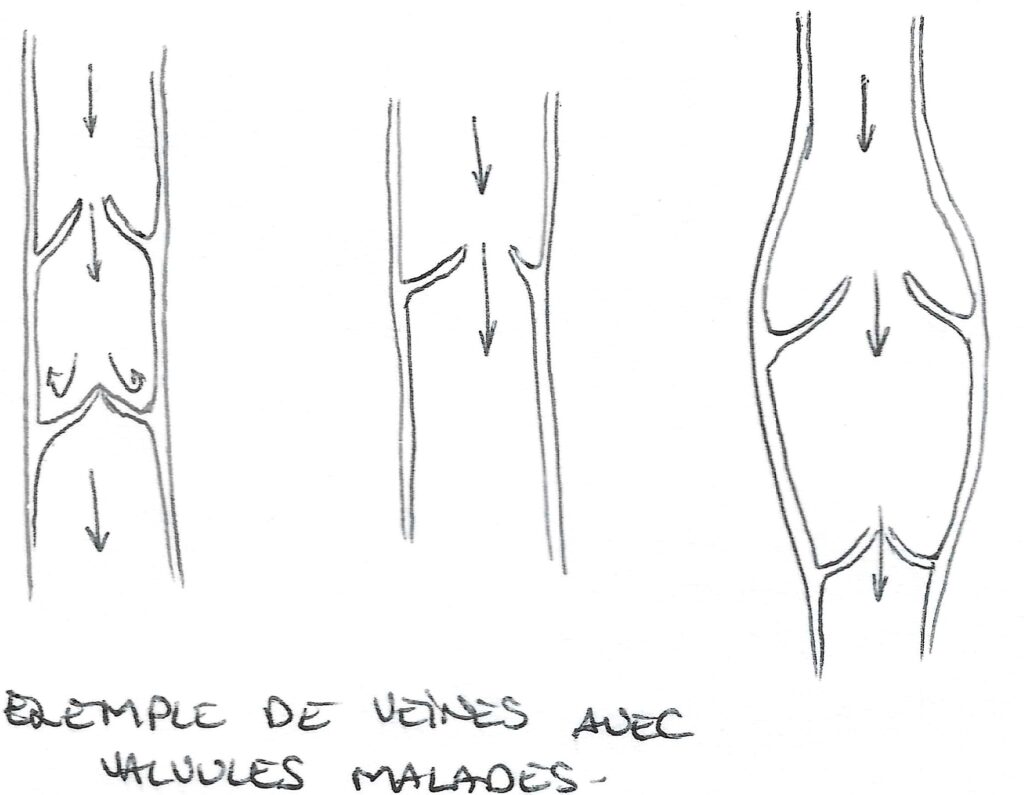

- valves, clapet anti-retour : « portes battantes » qui ne s’ouvrent que dans un seul sens, lors du passage du liquide.

L’insuffisance veineuse est un trouble du retour veineux. En général, elle est due à un mauvais fonctionnement de ces clapets. Ces derniers peuvent mal se fermer, ne pas se fermer du tout, être en nombre insuffisant, être mal formés.